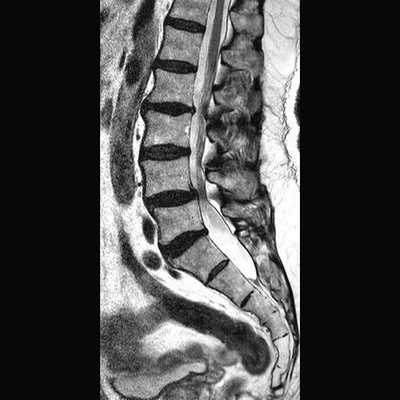

МРТ позвоночника. Сагиттальная Т2-взвешенная МРТ, срединный срез поясничного отдела. Показана нумерация позвонков, измерения позвоночного канала (черная линия). Т- дуральный мешок с ярким ликвором. L- желтая связка. Sacrum - крестец. D - межпозвоночный диск. Голубым выделен остистый отросток, желтым - тело позвонка, Голубые точки - ход корешков.

МРТ позвоночника. Парасагиттальная (околосрединная) Т2-взвешенная МРТ поясничного отдела. Красными стрелками показаны корешки.